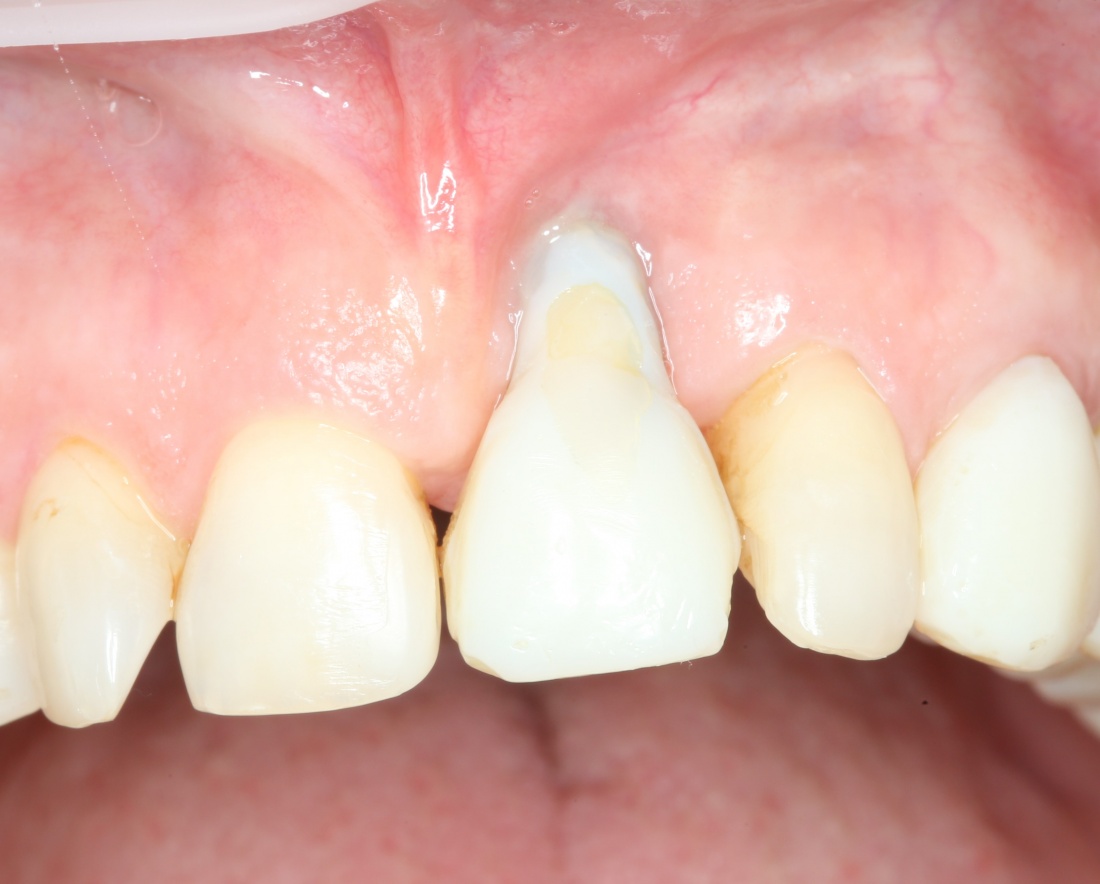

Рекомендации по установке имплантов. Для всех. Часть V.